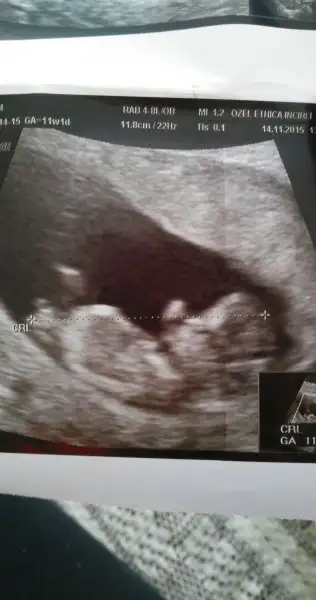

Gozunaydiñ cnm bebisin basi sagda darfarkk ettinizmi kizlar yani teorim tutuyor gıbı

Ben varım. 6 8 haftalar arası devam etti. 10 haftada tamamen kesildi. Suan 11+4 günlük bana gore hatta ultrasona görede 11+6;)